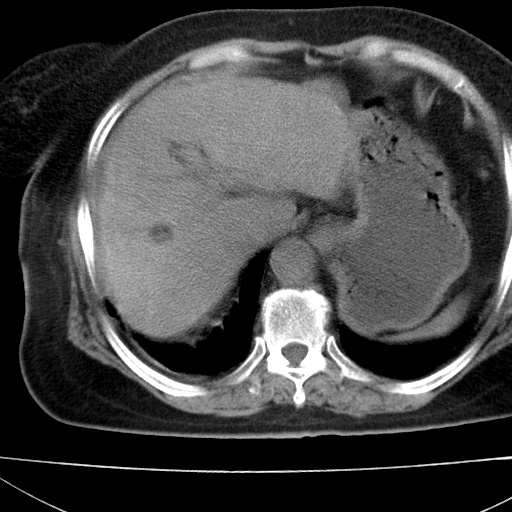

患者女74岁;右上腹胀痛1月,伴恶心,无发热;生活在疫水区。有术后病理及术后半年的追踪ct.

1)慢性血吸虫病(典型)。2)肝硬化。3)肝癌?4)胆囊炎。5)少量腹水。6)右侧少量胸腔积液。

支持.边缘见高密度线条样钙化影.

肝脏体积缩小,肝裂增宽,边缘不平呈波浪状,肝右叶见分隔状条索形钙化,亦见多结节低密度灶,边界不清,肝周可见少许液性暗区,胆囊增大内密度均匀,脾脏下缘低于脏脏的下缘,胸腔亦见液性暗区,余未见明显异常.

诊断:1肝硬化并慢性吸血虫病,脾肿大

2肝内占位,考虑肝癌可能性大,建议做增强

3胆囊炎, 4少量腹水及胸水

胆囊增大饱满,壁增厚。胆囊颈部见软组织密度影。临近肝右叶前段见片状低密度区,病灶下部见条状钙化,少量胸腹腔积液。意见:胆囊颈癌累及肝脏。

病人以胆囊癌手术的,病理结果为中分化腺癌。

现在看看肝右叶内圆形低密度影你们考虑什么呢?

肝内圆形低密度影考虑扩张的胆管

请看3mm重建像如下: